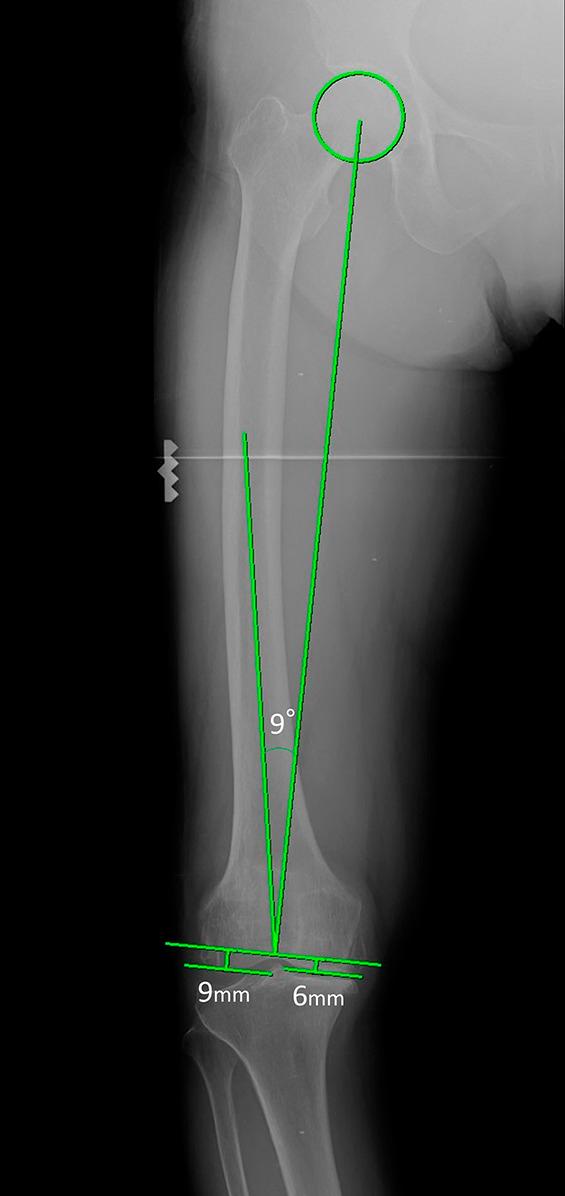

First, we resected 10 femoral Sawbones specimens using the AR-based navigation system and performed computed tomography (CT) to measure the resection angle of the distal part of the femur. We calculated the absolute values of the differences between angles measured using CT images and angles displayed on the smartphone screen of the navigation system. Second, we measured coronal alignment using standing long-leg radiographs for 72 patients undergoing TKA and compared the error in the resection angle between TKA using the AR-based navigation system and that using a conventional intramedullary guide.

In the experimental study, the absolute values of the differences between angles measured on CT images and angles displayed using the AR-based navigation system were 0.8° ± 0.5° (range, 0.3° to 1.9°) in the coronal plane and 0.6° ± 0.5° (range, 0.0° to 1.4°) in the sagittal plane. In the clinical study, the mean absolute value of the error in coronal alignment was significantly smaller in the AR-based navigation group than the intramedullary-guide group (1.1° ± 1.0° [range, 0.0° to 3.2°] compared with 2.2° ± 1.6° [range, 0.0° to 5.5°], respectively; 95% confidence interval, 0.5° to 1.8°; p < 0.001).